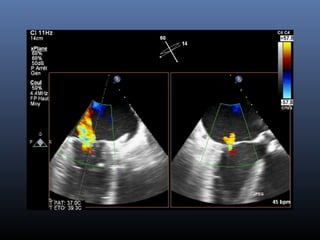

Echo post

Avant après